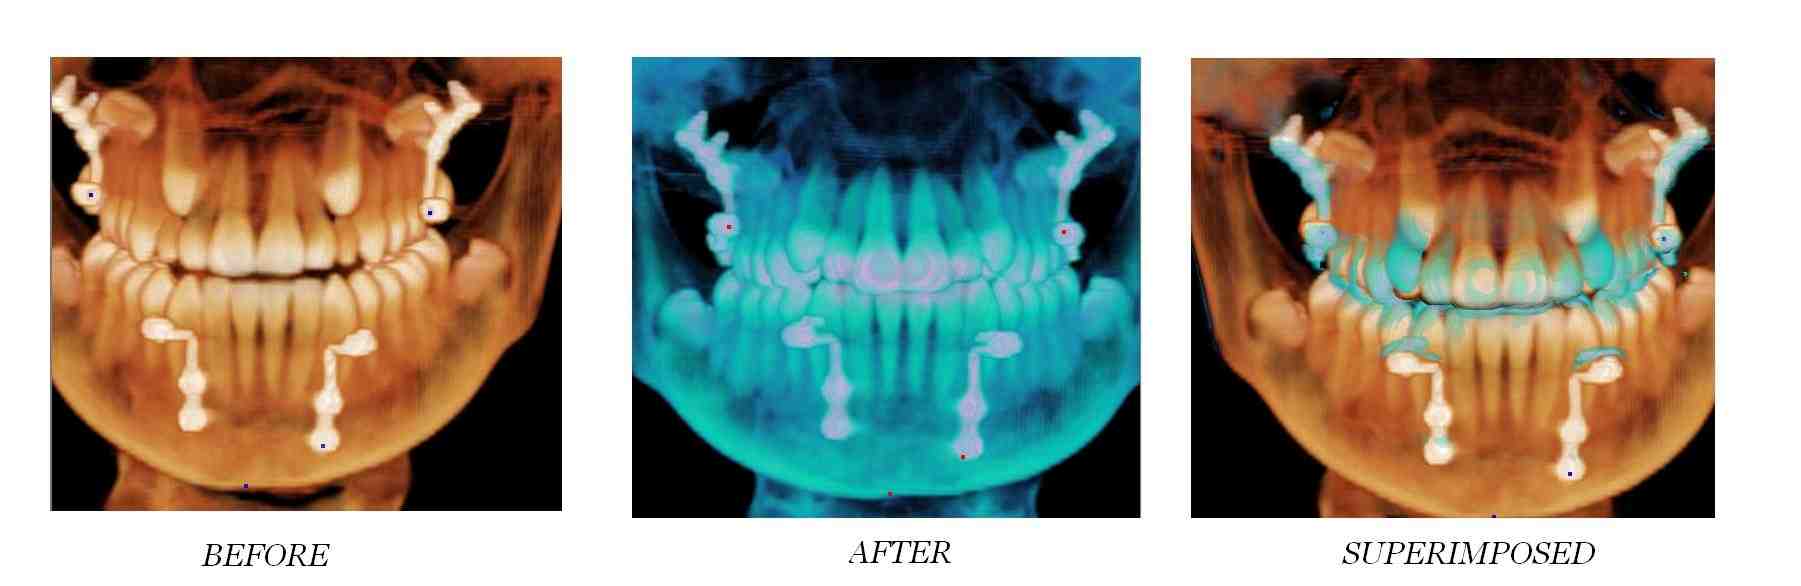

What is Peri Implantitis?

Peri-implantitis is a site specific infectious disease that causes an inflammatory process in soft tissue, and bone loss around an osseointegrated implant in function. Read also : All On 4 Dental Implants Cost.